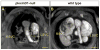

Background: Microcomputed tomography (micro-CT) has been used extensively in research to generate high-resolution 3D images of calcified tissues in small animals nondestructively. It has been especially useful for the characterization of skeletal mutations but limited in its utility for the analysis of soft tissue such as the cardiovascular system. Visualization of the cardiovascular system has been largely restricted to structures that can be filled with radiopaque intravascular contrast agents in adult animals. Recent ex vivo studies using osmium tetroxide, iodinated contrast agents, inorganic iodine, and phosphotungstic acid have demonstrated the ability to stain soft tissues differentially, allowing for high intertissue contrast in micro-CT images. In the present study, we demonstrate the application of this technology for visualization of cardiovascular structures in developing mouse embryos using Lugol solution (aqueous potassium iodide plus iodine).

Methods and results: We show the optimization of this method to obtain ex vivo micro-CT images of embryonic and neonatal mice with excellent soft-tissue contrast. We demonstrate the utility of this method to visualize key structures during cardiovascular development at various stages of embryogenesis. Our method benefits from the ease of sample preparation, low toxicity, and low cost. Furthermore, we show how multiple cardiac defects can be demonstrated by micro-CT in a single specimen with a known genetic lesion. Indeed, a previously undescribed cardiac venous abnormality is revealed in a PlexinD1 mutant mouse.

Conclusions: Micro-CT of iodine-stained tissue is a valuable technique for the characterization of cardiovascular development and defects in mouse models of congenital heart disease.